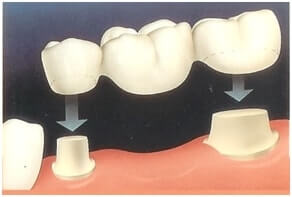

Prothèse unitaire métallique

1 examenExamens disponibles

PC S3 #1

Prothèse conjointe plurale

5 examensExamens disponibles

PC S5 #1

PC S5 #2

PC S5 #3

PC S5 #4

PC S5 #5

Prothèse conjointe à recouvrement partielle

3 examensExamens disponibles

PC S7 #1

PC S7 #2

PC S7 #3